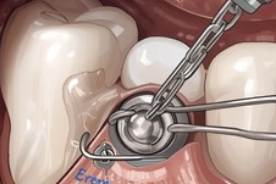

Dents de sagesse incluses

Aussi appelées "troisièmes molaires". Ces dents ne sont pas sorties complètement de la machoire et sont parfois complexes à extraire.

Extractions

dentaires multiples

Lorsqu'il y a plus de 6 dents à extraire, l'intervention sous anesthésie générale peut être adaptée